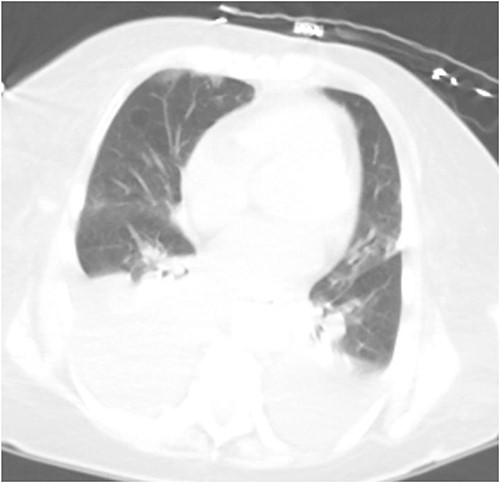

Repeat imaging was performed and revealed peri-hepatic ascites, significant anasarca and bilateral pleural effusions (Fig. 3) while the PCT remained in good position (Fig. 4). Bilateral chest tube placement and drainage of the pleural effusions revealed chylothorax and malignant cells. Cultures of both PCT output at the time of insertion and pleural fluid cultures grew no organisms.

Computed tomography (CT) chest demonstrating bilateral pleural effusions.